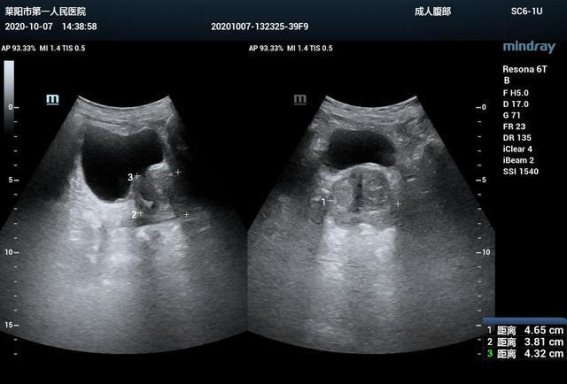

前列腺增生的早期发现依赖于科学体检,包括B超、直肠指检及前列腺特异性抗原(PSA)检测。PSA是一种由前列腺分泌的蛋白质,其血液水平升高可能提示前列腺结构异常或炎症。中年男性应每年进行一次相关检查,以便及时了解腺体状况。对于症状轻微、体积较小的患者,通过规律运动、改善饮食和代谢状态等生活方式干预即可延缓疾病发展;而症状明显或并发症高风险者,医生可能建议药物治疗或必要时手术干预。